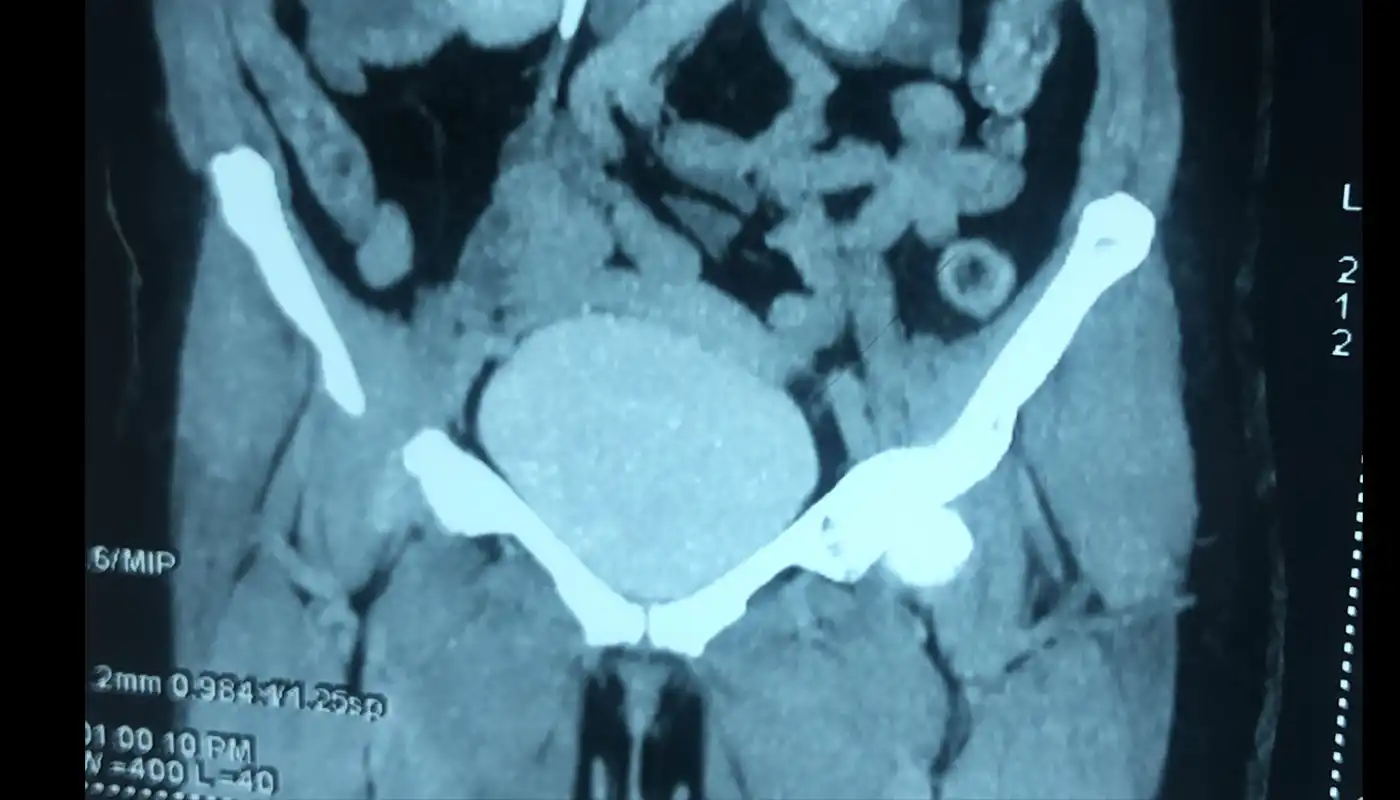

• Kidney Cancer: It accounts for 3-4 % of total cancers leading to 2-3 cases per lakh population in India per year, this cancer is very well treatable with complete cure and preservation of the kidney as well if it its detected at early stages, Presenting symptoms are hematuria, pain and lump, however it remains asymptomatic till advance stages hence patient don’t visit hospital. Most of the early detected kidney cancers are incidentally detected.

• Bladder Cancer: bladder cancer is 4th most common cancer in males and 8th most common cancer in females worldwide. Most common presentation is painless hematuria. It most commonly occurs in 6th decade of life. Smoking remains most important risk factor responsible for 48 to 74% of bladder . risk of bladder cancer due to smoking is dose and duration dependent. If detected in early stage most of the bladder cancers can be managed endoscopically without major surgery, however in muscle invasive stage urinary bladder needs to be removed for complete cure from cancer, further advance stages are treated with multidisciplinary approach using surgery , chemotherapy and immunotherapy.